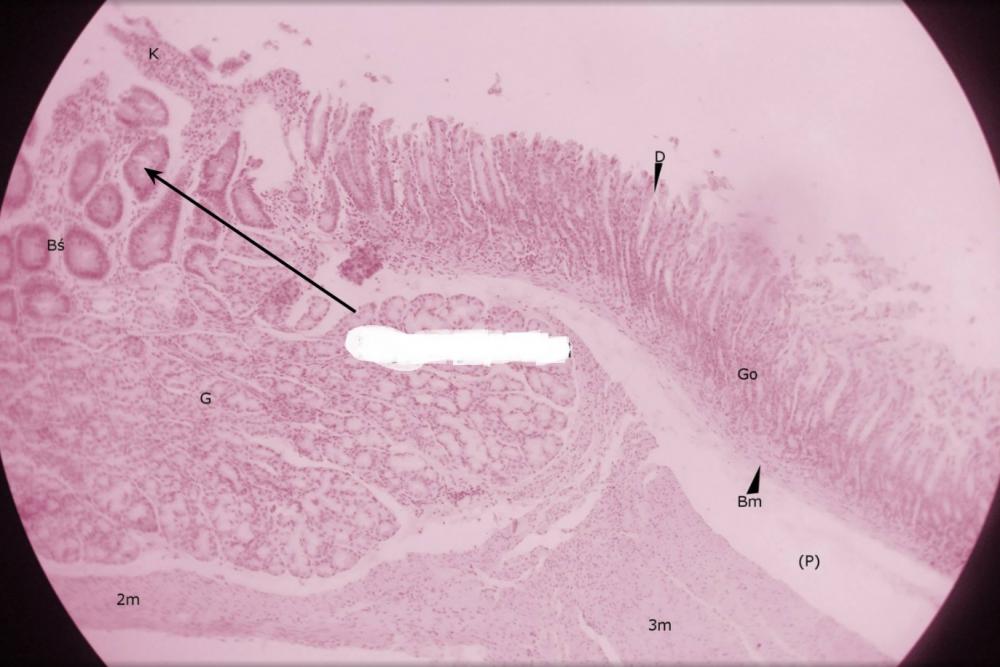

dołki żołądkowe (przejście żołądka w dwunastnicę)

pólka żołądkowe (przejście żołądka w dwunastnicę)

rozgałęzione gruczoły cewkowe - odźwiernikowe (przejście żołądka w dwunastnicę)

kosmek jelitowy (przejście żołądka w dwunastnicę)

krypta jelitowa (przejście żołądka w dwunastnicę)

gruczoły Brunnera (przejście żołądka w dwunastnicę)

błona mięśniowa, składająca się z warstwy okrężnej o podłużnej (przejście żołądka w dwunastnicę)

miejsce po błonie podśluzowej (przejście żołądka w dwunastnicę)

blaszka mięśniowa błony śluzowej (przejście żołądka w dwunastnicę)

gruba, trójwarstwowa mięśniówka żołądka (przejście żołądka w dwunastnicę)